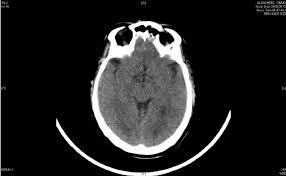

Ct Head Scan Familydoctor Org

Ct Head Scan Familydoctor Org from familydoctor.org